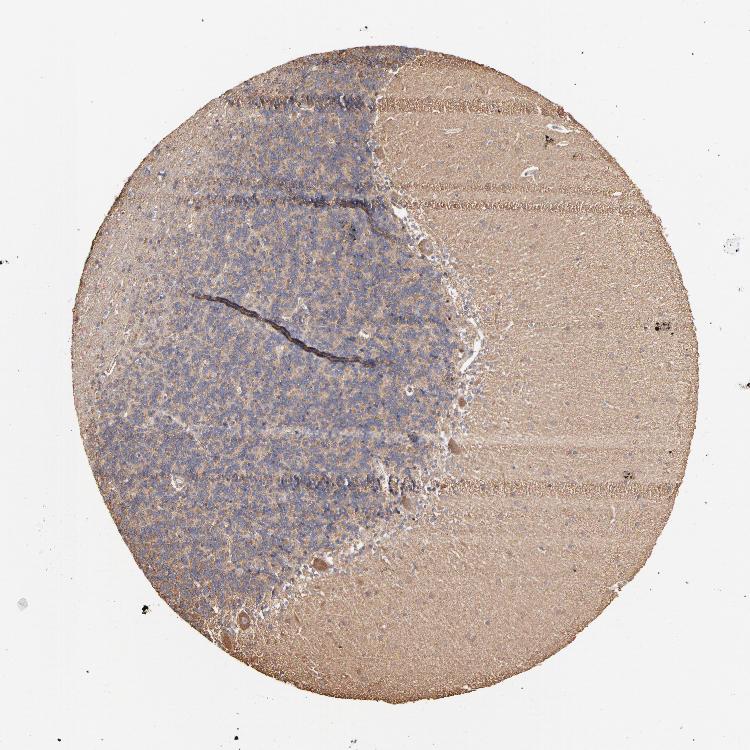

CEREBELLUM - Antibody stainingi

Antibody staining in the annotated cell types in the current human tissue is reported as not detected, low, medium, or high, based on conventional immunohistochemistry profiling in selected tissues. This score is based on the combination of the staining intensity and fraction of stained cells.

Each image is clickable and will lead to virtual microscopy that enables deeper exploration of all samples and also displays staining intensity scores, fraction scores and subcellular localization as well as patient and tissue information for each sample.

Antibody HPA003004Antibody HPA005819

Purkinje cells MediumNot detected

Cells in granular layer Not detectedLow

Cells in molecular layer Not detectedNot detected